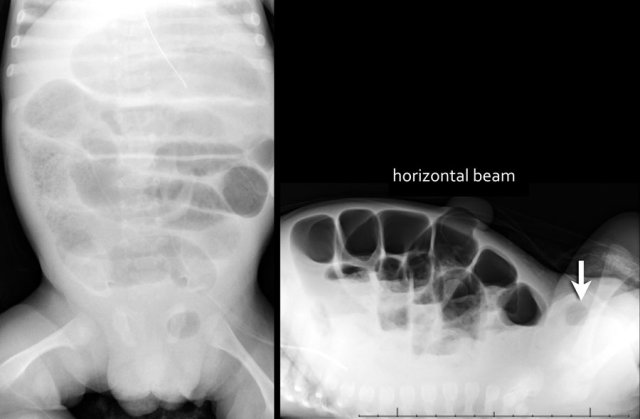

The images show a typical case of NEC with pneumatosis intestinalis.

On the horizontal beam image there is no sign of free air.

Here images of a neonate who developed NEC.

At this early stage the radiograph only shows non-specific bowel dilatation.

At this stage you cannot make the diagnosis.